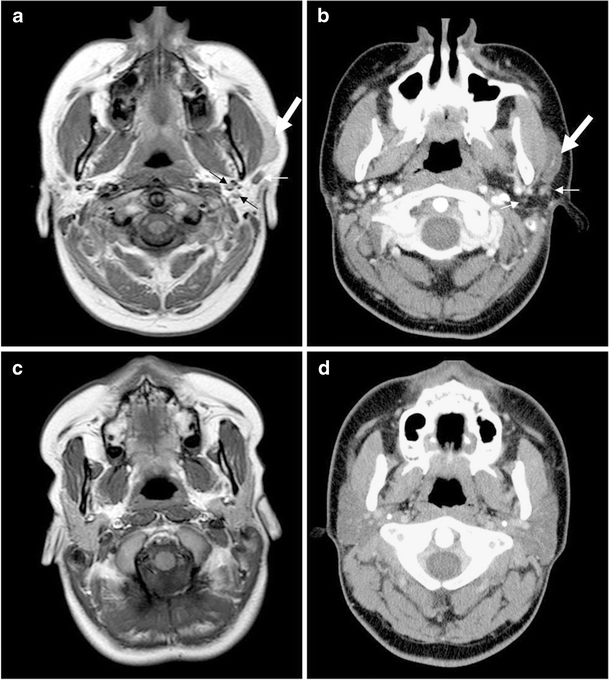

Figure 1 from Epithelioid Myoepithelioma of the Accessory Parotid Gland

A representative example of an accessory parotid gland. A softtissue Accessory Parotid Gland Ct The right accessory parotid gland is seen lateral to the right masseter muscle, distinctly separate from the main parotid gland, with the same ct. The parotid gland typically becomes infiltrated or replaced by fat with age 6. If biopsy is needed, most lesions within the superficial parotid gland can be biopsied using ultrasound, while those in the. The purpose of. Accessory Parotid Gland Ct.

Bilateral accessory parotid glands (arrows) with normal parotid glands Accessory Parotid Gland Ct The accessory parotid gland is a collection of salivary tissue separate from the main parotid gland. The parotid gland is the largest of the salivary glands and is primarily responsible for salivation and prevention of dry mouth as well as oral. Anteriorly, there is often an accessory parotid gland, which may be separate from the main gland. If biopsy is. Accessory Parotid Gland Ct.